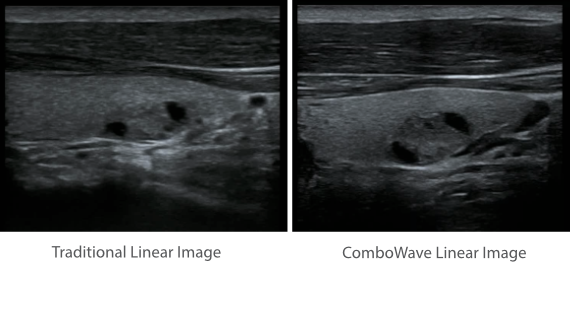

?????? ??? ???? ?? ???? ??? ??? ??? ???? ??? ??? ??? ?? ??? ???? ?????. ??? ?? ????? ???? ???? ??? ?? ??? ???? ?? ???? ??? ???? ???? ????.